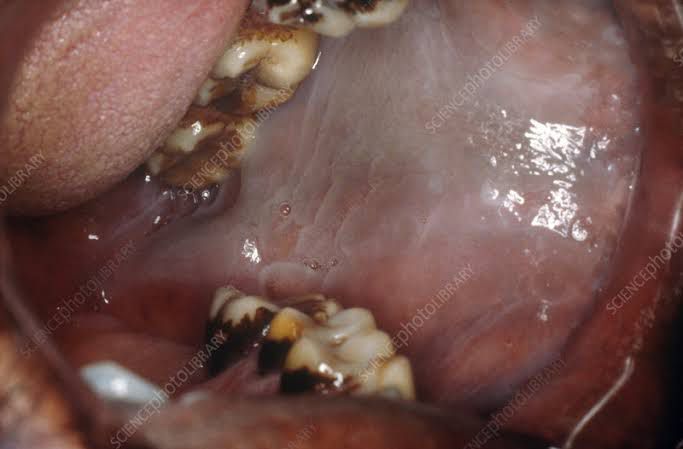

Leukoedema

Leukoedema is a white or whitish-gray edematous lesion of the buccal and labial oral mucosa. The lesions may be diffuse or patchy, and are usually asymptomatic. Leukoedema may be confused with leukoplakia, Darier's disease, white sponge nevus, pachyonychia congenita, or candidal infection.